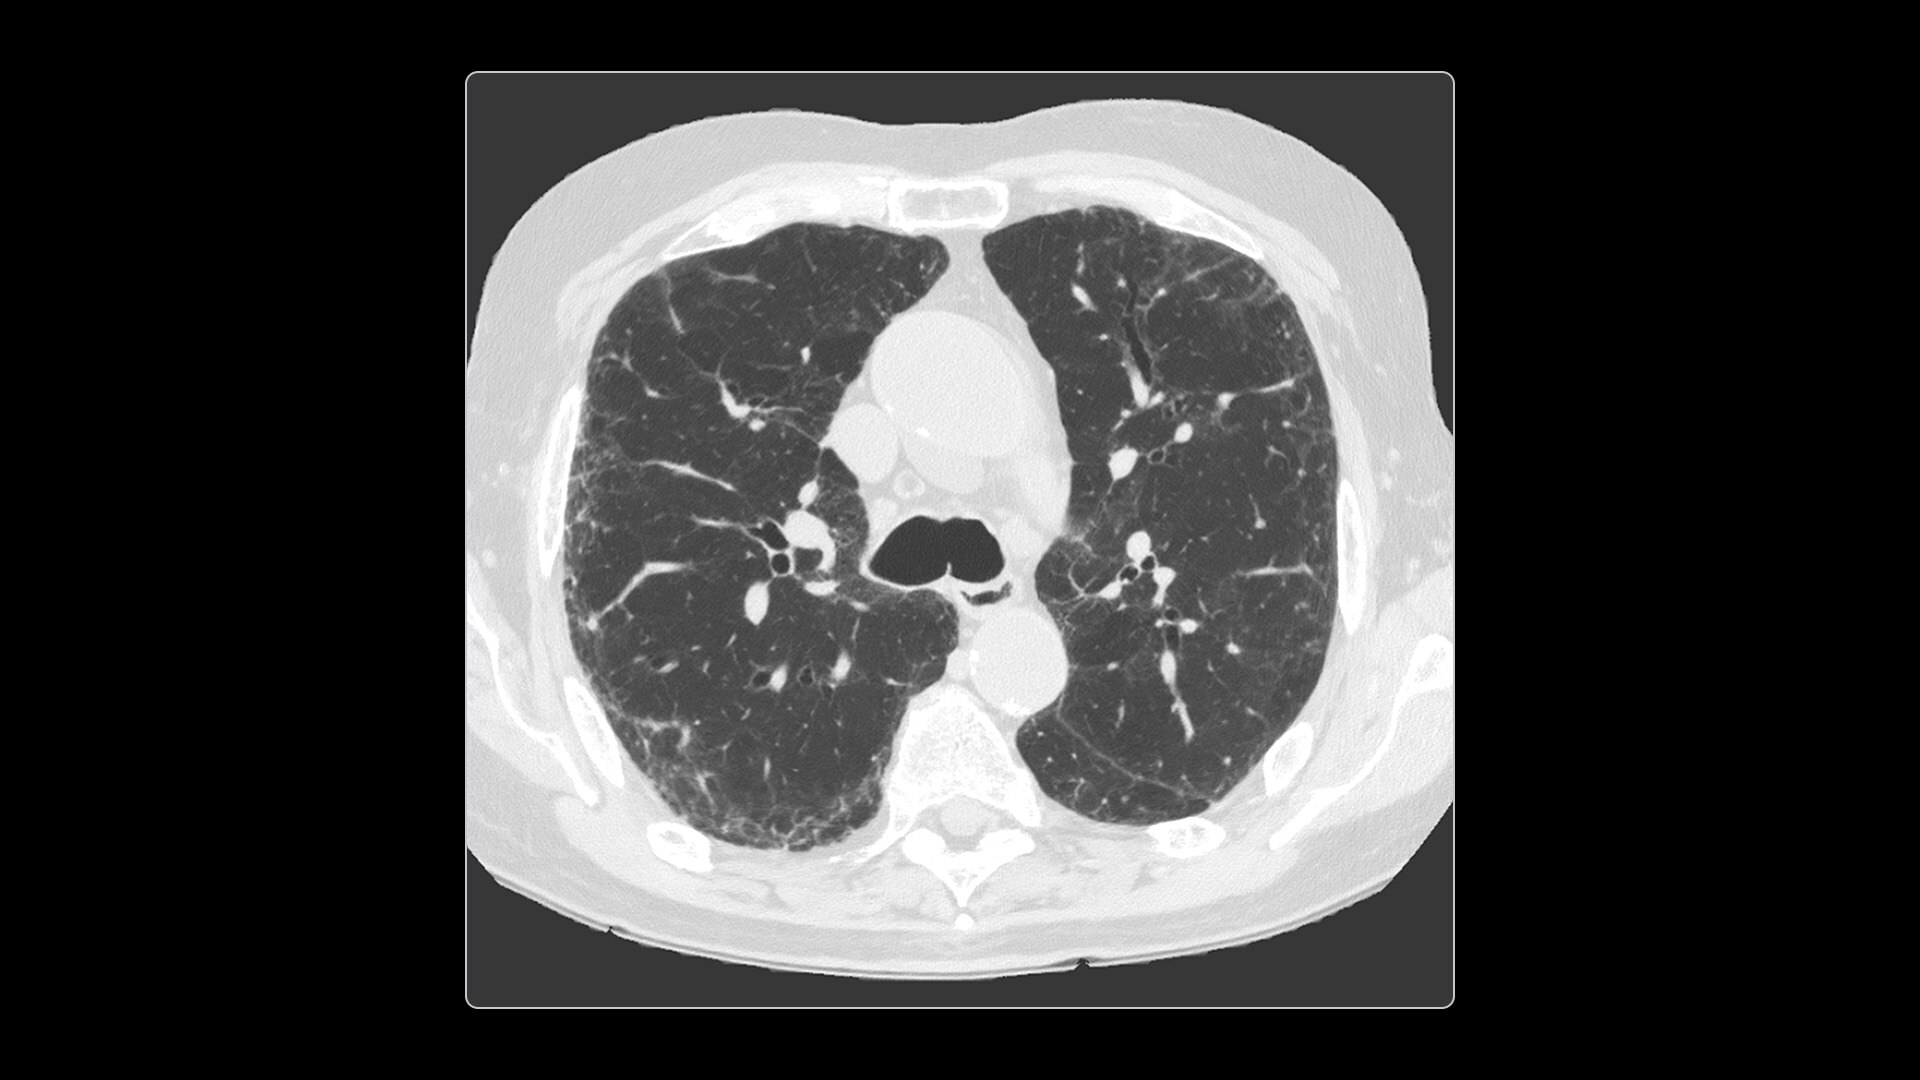

Ultra-high definition imaging

Photonova Spectra provides wide coverage in ultra-high definition imaging with exceptional acquisition speeds, designed to allow you to see your patient’s anatomy in exquisite detail.

With ultra-high spatial resolution scanning capability, Photonova Spectra is designed to help you see incredibly fine details, such as coronary plaque delineation, small microvascular vessels and even tiny structures of the inner ear.

Experience our industry-leading 8 cm detector coverage, combined with up to 0.23 sec rotation speed and ultra-high sampling rates featuring a 50 cm field of view (FOV) in all scan modes. This enables wide-coverage ultra-high definition imaging with reduced organ movement for exceptional image clarity.